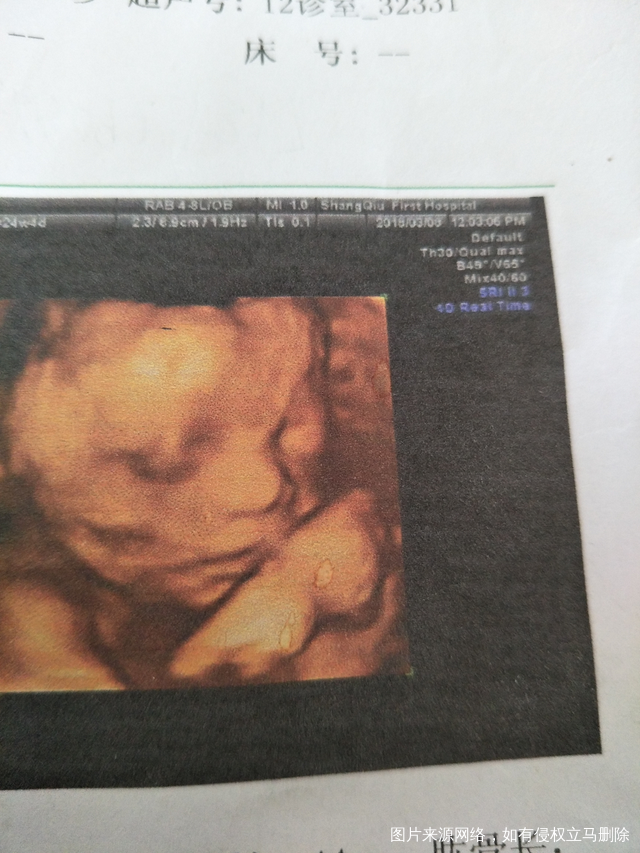

医生帮我看看这个四维图

胎儿嘴唇右边我看着有一点白色的,胎儿手腕上面接近嘴巴那一点白色的是什么